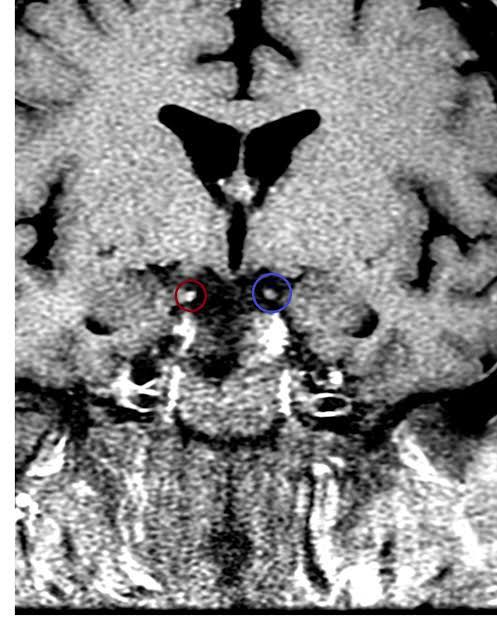

The diagnosis of MFS is clinical. It depends on identifying the characteristic features from the symptoms and physical examination. There is no definitive diagnostic test. Antibodies against ganglioside GQ1b support the diagnosis but also occur in Bickerstaff brainstem encephalitis.